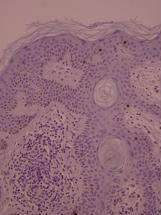

ki-67 staining of reticulo-acanthotic type of SKs.

ki-67 staining of reticulo-acanthotic type of SKs.

ki-67 staining of reticulo-acanthotic type of SKs.

ki-67 staining of reticulo-acanthotic type of SKs.